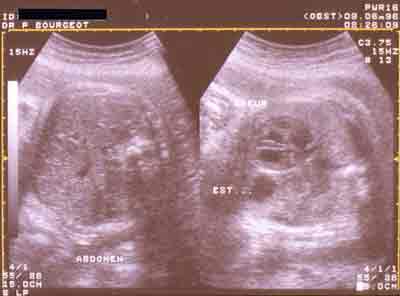

Hernie diaphragmatique gauche. A noter l’absence d’estomac sur le cliché de gauche

(coupe transversale de l’abdomen)